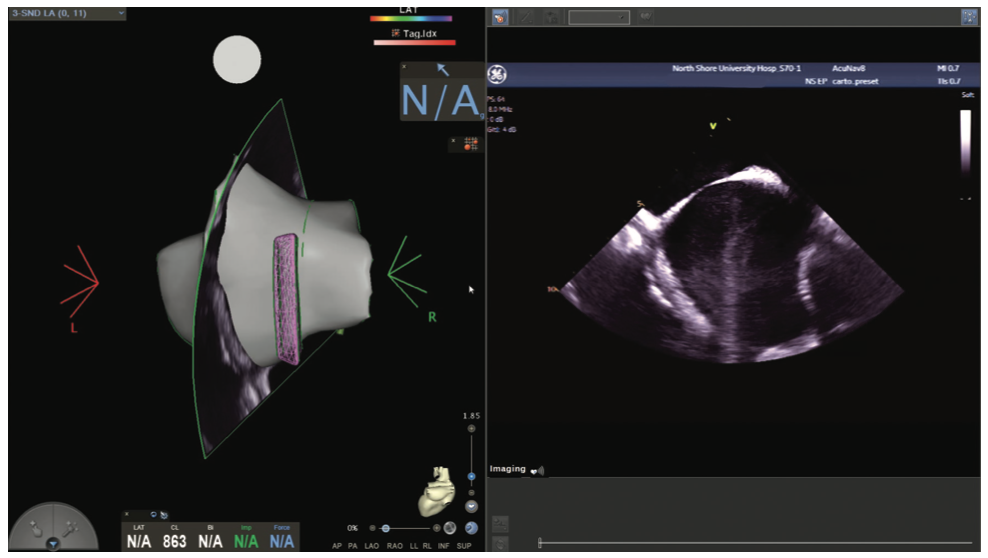

Figures/Videos 1-10 demonstrate the process of navigation from groin access to the heart to create biatrial geometry, localize the esophagus, and gain transseptal access. Many currently practicing electrophysiologists use very little fluoroscopy to map and ablate the left atrium (LA) with the current multielectrode catheters and EAM systems once transseptal access is obtained.

Video 11a and Figure 11b show the voltage map of the LA as well as the pliability of the Pentaray spline catheter to adapt its shape to vessels (a right middle vein) and the endocardium.